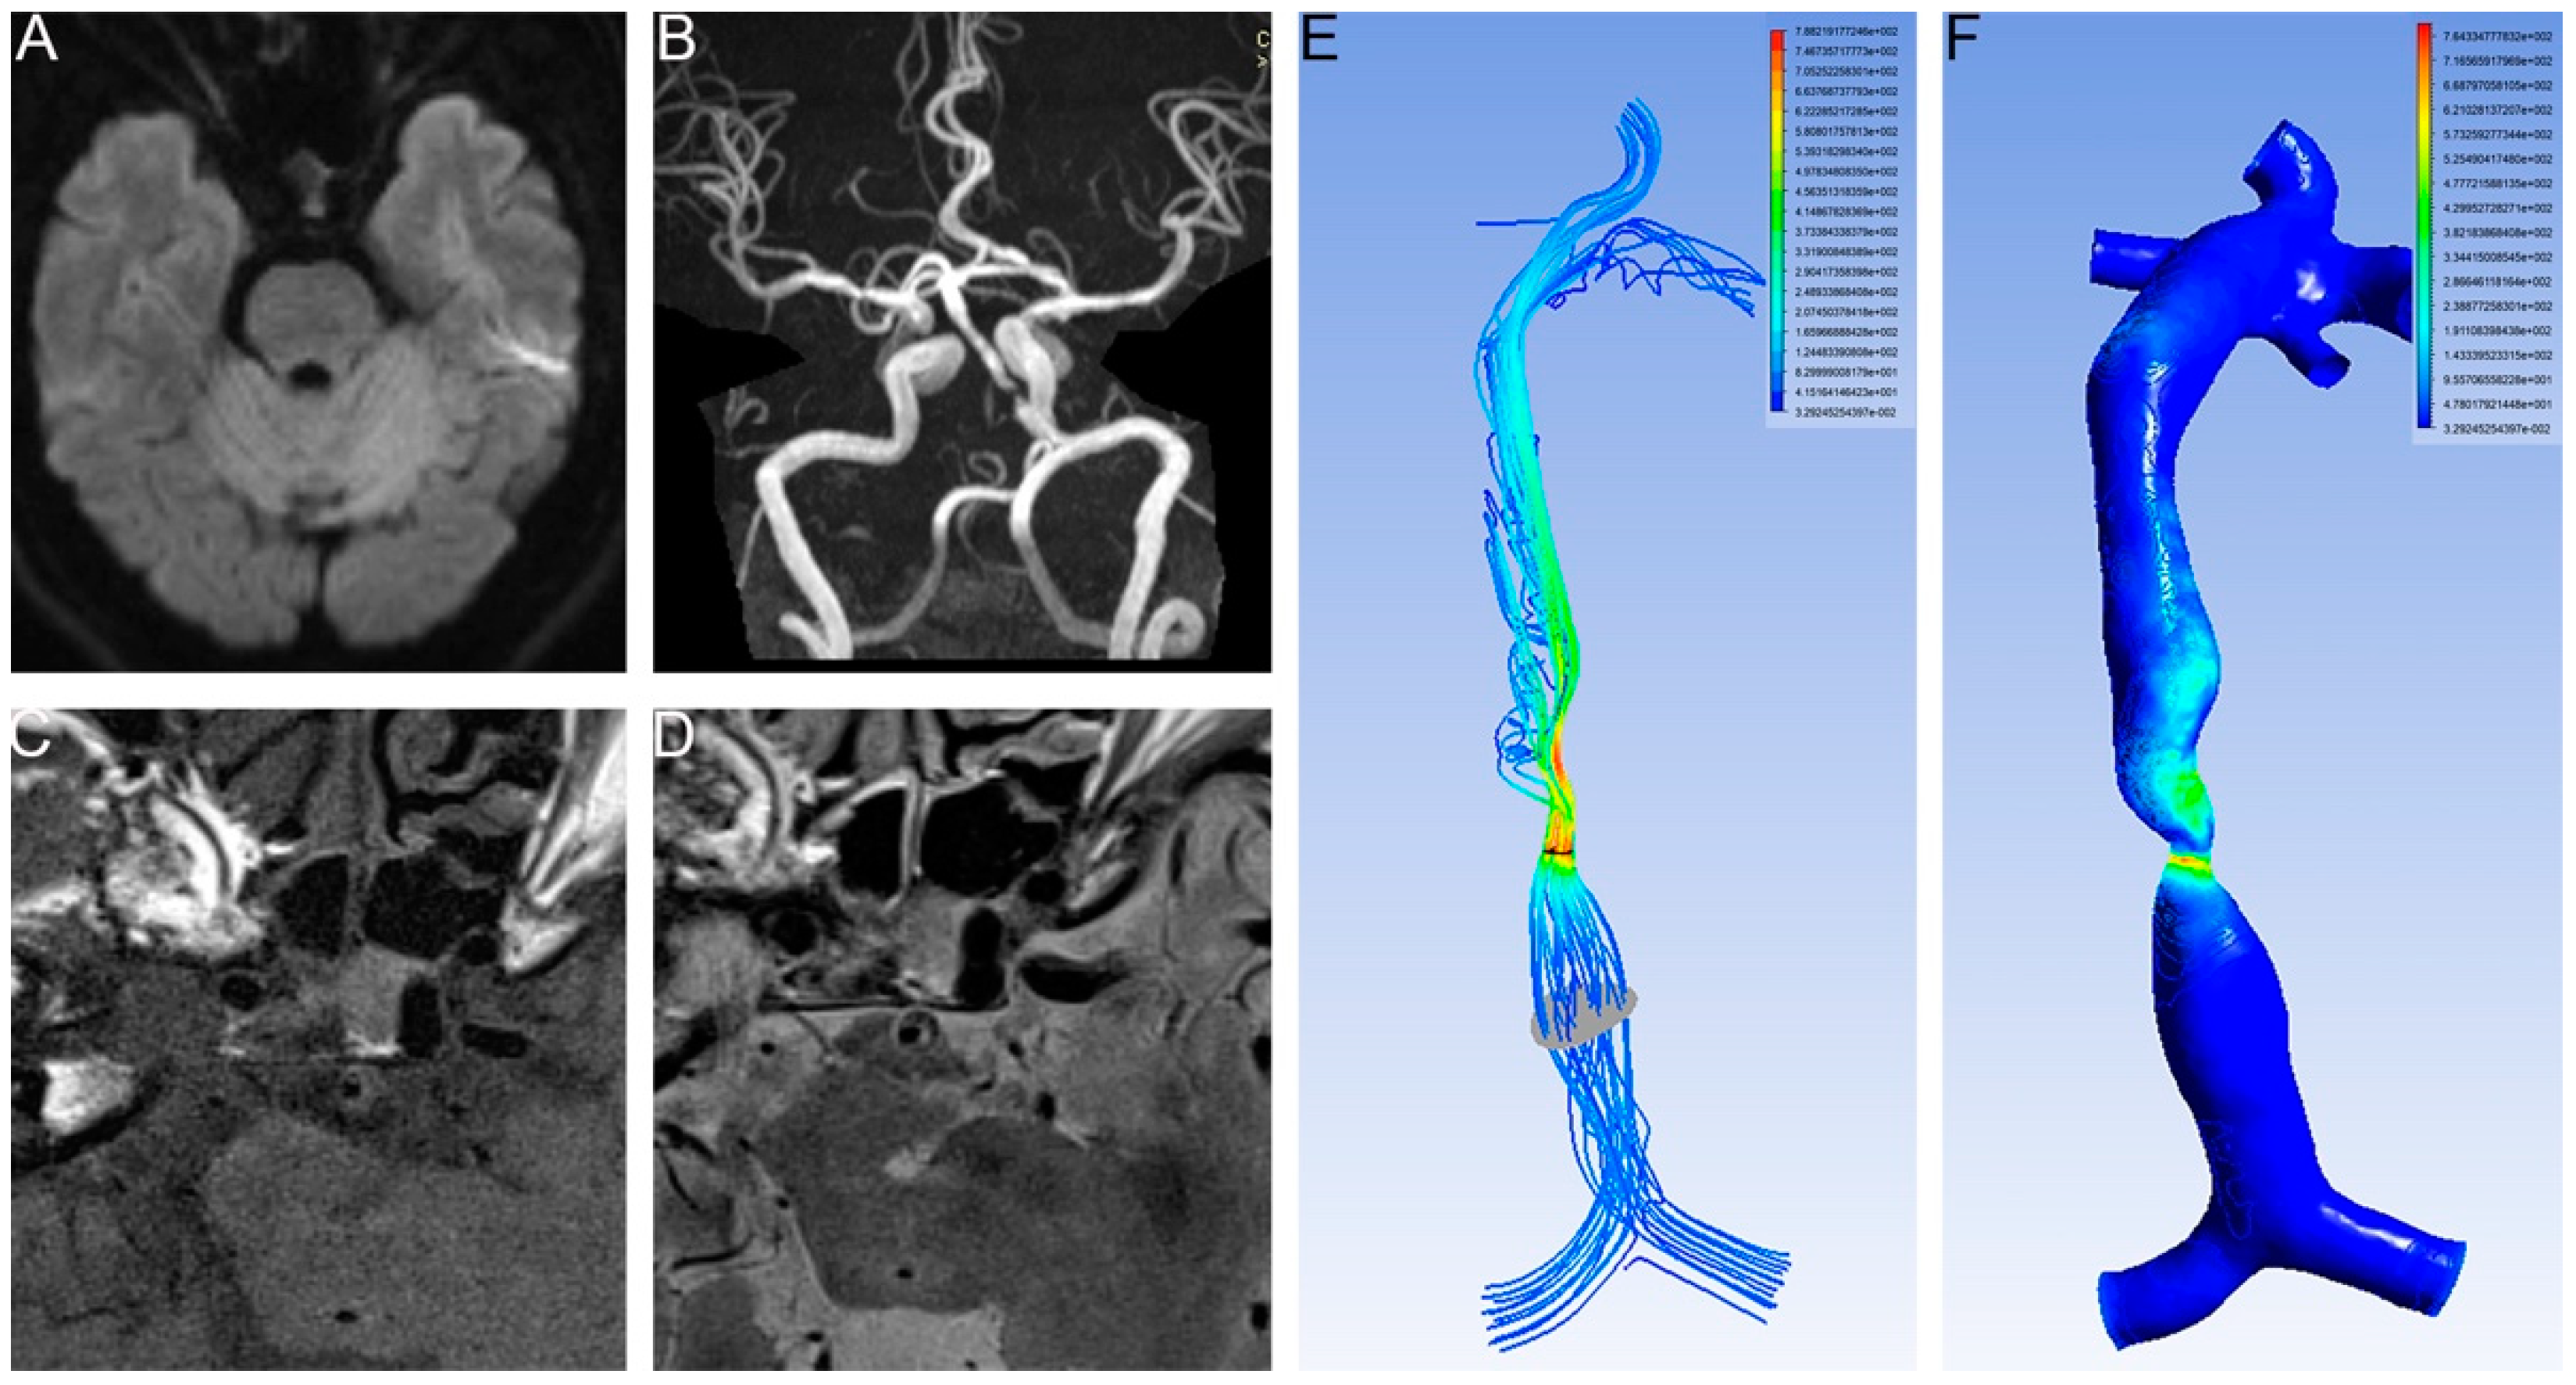

The stenotic WSS was measured at the most severely narrowed cross-section. The proximal WSS was measured at the normal vessel segment proximal to the plaque (Figure 1). The WSS ratio was defined as follows: WSS ratio = Stenotic WSS/ proximal WSS.

Figure 1.

No infarction occurred in the lower proximal WSS. (A) DWI showed no infarction. (B) T2 images of HR MRI showed intact fibrous cap. (C) T1 images of HR MRI showed intact fibrous cap. (D) T2 images of HR MRI showed intact fibrous cap. (E) Velocity of BA. The planes (gray and dark) represent the place we measured. (F) WSS of BA. Proximal WSS was 2.88 Pa and stenotic WSS was 490.78 Pa.

An RFC was identified in the 35 patients (19.9%, Figure 3). An RFC was significantly associated with acute infarction (27/35 vs. 96/141, p < 0.05, Table 1, Figure 1 and Figure 3).

Higher proximal WSS related with stroke. (A) DWI showed an infarction located in the pontine. (B) T2 images of HR MRI showed RFC. (C) Velocity of BA. (D) WSS of BA. Proximal WSS was 7.34 Pa and stenotic WSS was 559.51 Pa.

The proximal WSS was higher in the patients with an RFC than in those without an RFC (8.68 ± 17.60 vs. 8.07 ± 4.55, p < 0.05, Table 1). The multivariable logistic regression analysis showed that proximal WSS was an independent risk factor for RFC (1.564, 95% CI 1.101–2.222, p < 0.05, Table 2).

The cut-off value of the proximal WSS was 4.84 Pa (area under the ROC curve 0.732, p = 0.008, 95% CI 0.565–0.899). In one patient with a lower proximal WSS, there was no infarction (Figure 3).